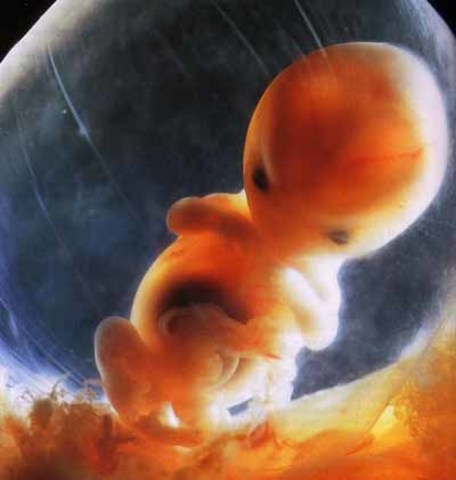

• semana 3, 4 y 5 de embarazo

semana 3, 4 y 5 de embarazo

En la semana tres se empieza a formar el sistema nerviso el embrión está formado por 3 capas célulares, la capa superior el ectodermo, donde se desarrolla el cerebro y varias regiones del sistema nervioso central, así como la epidermis las glándulas de la piel, uñas y el pelo. La capa media el mesodermo de donde cxrece el corazón, el sistema circulatorio, los huesos, los músculos, los riñones y los órganos de reproducción y por último la tercera capa mas interna , el endodermo, que es un tubo.

• semana 8 y 9 de embarazo

semana 8 y 9 de embarazo

Hacia el final de la semana 8 el cuerpo estará formado, así como tosoa sus órganos y terminará el periodo embrionario. Dejará de ser un embrión para convertirse en feto en la semana 9 crecen los dedos de las manos y de los pies. La cabeza es desproporcionalmente grande y construye la mitad del embrión. La región del cuerpo se ha formado. T5iene un cuerpo muy flexible ya no tiene huesos.